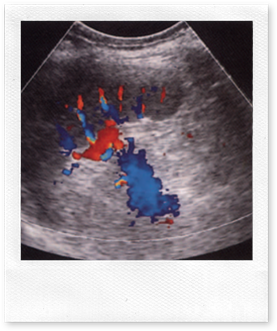

Left coronal view of the normal spleen demonstrating the main splenic artery and vein at the hilum.

The normal spleen has a fine, homogeneous texture, with smooth margins and a pointed inferior edge. It has similar echogenicity to the liver but may be slightly hypo- or hyperechoic in some subjects. Sound attenuation through the spleen is less than that through the liver, requiring the operator to ‘flatten’ the time gain compensation controls in order to maintain an even level of echoes throughout the organ. The main splenic artery and vein and their branches may be demonstrated at the splenic hilum (Fig.below).